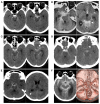

Perimesencephalic nonaneurysmal subarachnoid hemorrhage (PNSAH) is a distinctive disease, representing SAH centered in perimesencephalic cisterns, with negative angiography findings. In recent years, the number of patients with PNSAH has increased significantly; however, the knowledge of PNSAH is insufficient. Therefore, we performed a review of the literature from a PubMed search and recounted our understanding of PNSAH. In this review, we summarized that current high-resolution computed tomography angiography is an acceptable replacement for digital subtraction angiography to rule out aneurysms in PNSAH with strict criteria. The current hypothesis about the etiology of PNSAH is that there is deep vein rupture from aberrant venous anatomy and increased intracranial venous pressure. PNSAH is associated with mild symptoms and lower rates of hydrocephalus and symptomatic vasospasm. For PNSAH, conservative treatment has been the mainstream treatment. PNSAH has a benign clinical course and an excellent prognosis; in long-term follow-up, re-bleeding and death were uncommon.